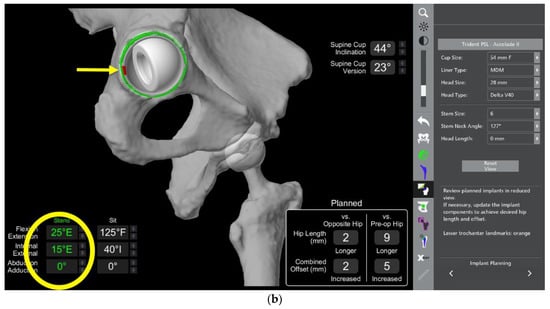

- In this case, the native femoral retroversion (−6 degrees) posed a challenge in avoiding impingement (Figure 7). Upon assessing VROM, bone-on-bone and implant-on-implant impingement in deep flexion were noted (Figure 8). Using the robotic software, the planned femoral version was corrected to +16 in the femoral broach (Figure 9a,b).

- The robotic software also enables preoperative and intraoperative visualisation of the anticipated postoperative X-rays accounting for any changes to the plan. In addition, the software allows for calculation of changes to the leg length offset compared to the preoperative and contralateral hips. In this case, the leg length was 1 mm longer compared to the opposite hip, and the combined offset was 6 mm increased compared to that preoperatively (Figure 12a,b).